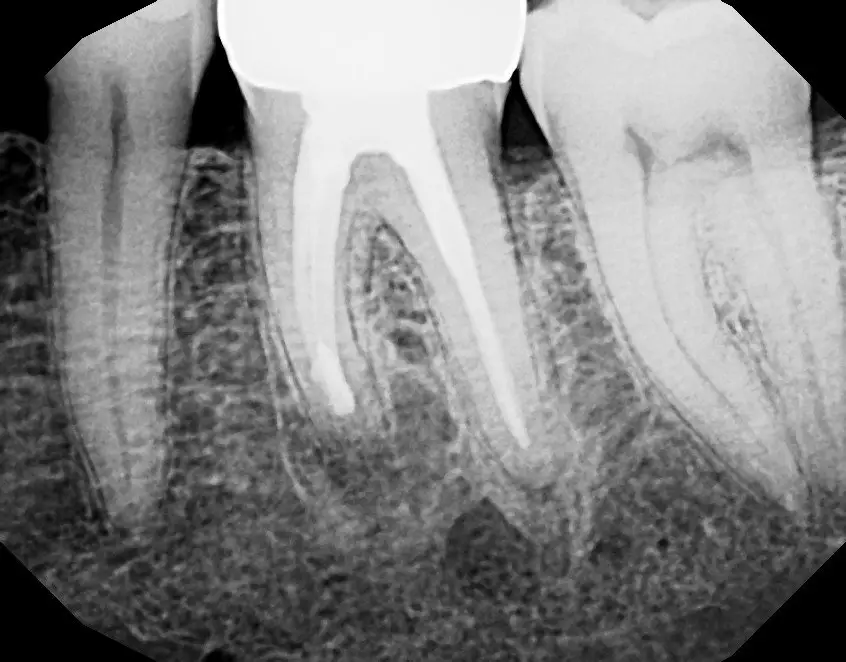

See the Difference Specialist Care Makes

Compare real treatment results through detailed before-and-after X-rays, showing how expert care restores dental health, precision, and long-term outcomes.